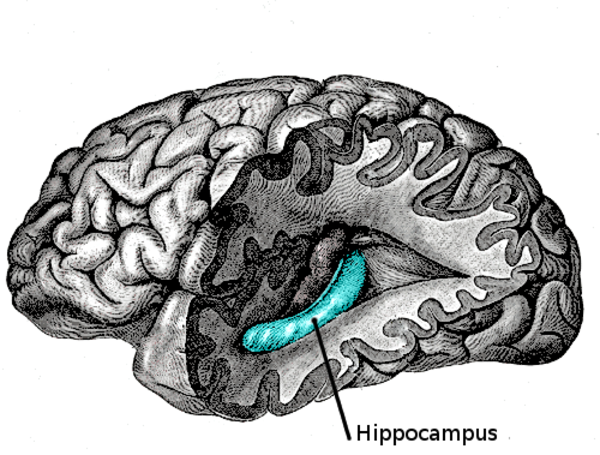

למעשה, החלק של המוח שמאחסן את הזיכרונות גם כותב זיכרונות חשובים על חשבון זיכרונות ישנים ולא חשובים.

אבל האינטליגנציה של המוח השוכח לא מסתיימת שם. היא גם עוזרת לנו למיין זיכרונות ישנים שאנחנו כבר לא צריכים, כדי שיהיה לנו מקום לזיכרונות חדשים וחשובים יותר.